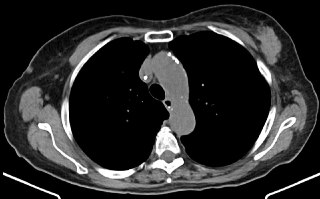

Спочатку, цікаве спостереження, за яким розподіл голосів за різні нозології в цьому випадку не сильно змінився після додавання даних МРТ. Тому, додаємо ще одне, фінальне дослідження, яке трапилося з пацієнткою відносно найпізнішим, а саме – банальна нативна КТ грудної клітки, пару зображень з якої ви бачите (за бажання погортати повністю – ось за цим посиланням). І ця КТ додає дані завдяки яким все доволі швидко стає на свої місця. Гарно помітна маса у лівій грудній залозі та інфільтрати/лімфаденопатія в іпсилатеральній аксилі. Разом це все чудово вкладається в метастатичну лобулярну карциному грудної залози, яка в кінці кінців і була верифікована при лапароскопічній біопсії перитонеальних уражень.

Лобулярна карцинома грудної залози – цікава та особлива пухлина, яка полюбляє «нетипові» для більш звичної NST протокової карциноми патерни метастазування, зокрема з перитонеальними ураженнями, окремими метастазами в орбіти, структури травного каналу, які часто мають вигляд «повзучих інфільтратів», а не окремих вузликів, вузлів чи мас.